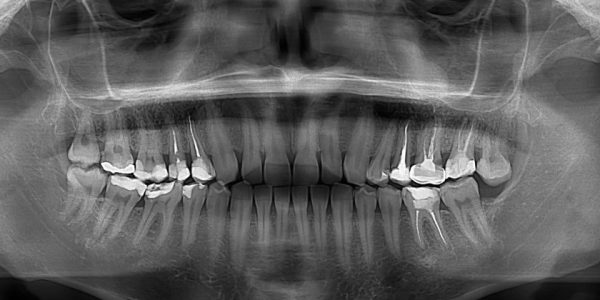

Understanding How Do Cavities Look Like On X-Ray: A Guide

Cavities on an x-ray appear as dark spots or areas of shadowing, indicating tooth decay or damage. These blemishes, formed due to demineralization, are crucial to detect early for effective treatment. Regular x-rays help dentists pinpoint cavities hidden from the…